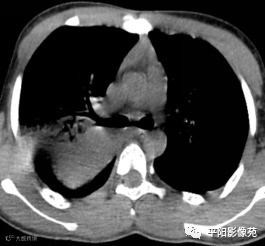

10天后再次复查CT:较前有所好转

影像特征:X线片右肺中上野片状高密度影,下缘以叶间裂为界,上缘及外侧缘模糊;CT位于右肺上叶后段,呈片状实变影,内见支气管影,边缘模糊。

影像诊断:右肺上叶大叶性肺炎。